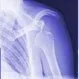

Dislocated ShoulderThe shoulder is the most often dislocated joint in the body due to its mobility. A dislocated shoulder occurs when the head of the humerus is dislocated from its socket. Symptoms of a shoulder dislocation include nausea and vomiting, lightheadedness, weakness, and sweating. There are various methods of reducing a dislocation and returning the humeral head to its normal place.

Rotator Cuff Tear and InjuryRotator cuff tear and injury is damage to any of the four tendons that stabilize the shoulder joint. Shoulder pain and tenderness are common symptoms. Rotator cuff tear and injury treatment depends on the severity of the shoulder injury.

What Are the Most Common Shoulder Injuries?The shoulder injury is an injury to any of the structures in the shoulder joint, including bones, muscles, tendons, ligaments, and cartilages. Shoulders are easily injured because they have a complex structure that provides a wide range of motion. They are the most mobile joints in the body and consequently, the most unstable.